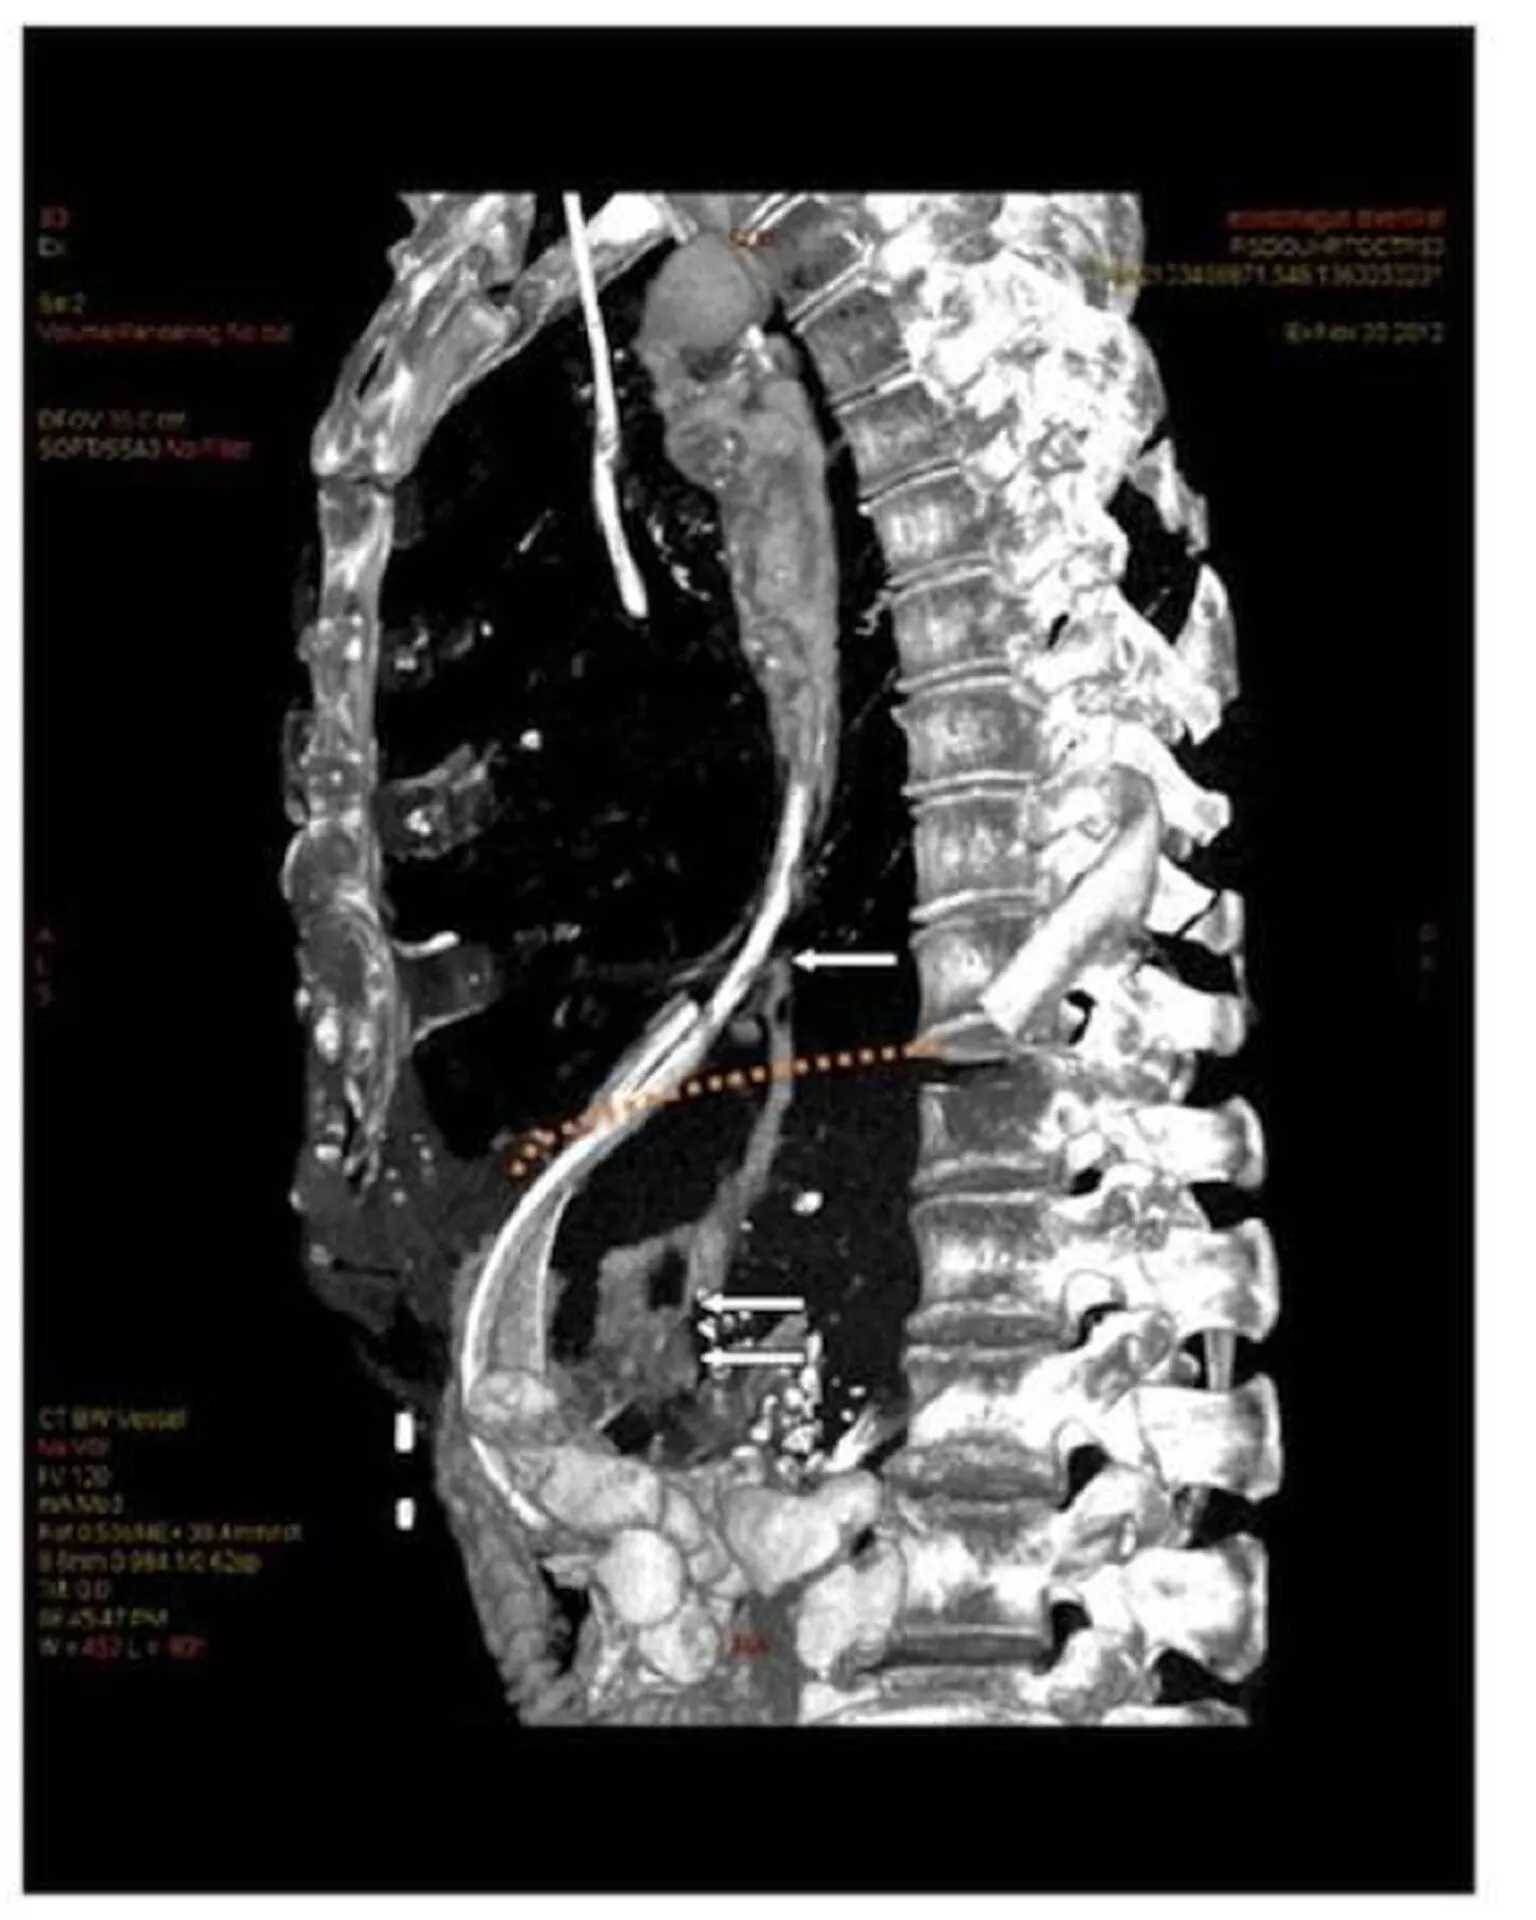

A few days after admission, placement of a new PEG tube was contemplated, and prior to this, a thoracoabdominal computed tomography with intravenous and oral contrast was performed. The CT scan demonstrated left side pleural effusion, dilatation of the mid-esophagus (mega-esophagus), and surprisingly a gastrointestinal leakage below the diaphragm at mid-level of the minor curvature of the stomach (Fig. 1).

Figure 1: Reconstruction of CT-scan with contrast

a) The orange line demonstrates the location of diaphragm at the cranial surface of the liver.

b) Upper arrow indicates the division between the proximal part of the diverticulum and esophagus.

c) Middle arrow demonstrates a fistula in the distal part of the diverticulum with contrast leakage.

d) Lower arrow show the contrast leakage in the abdomen.